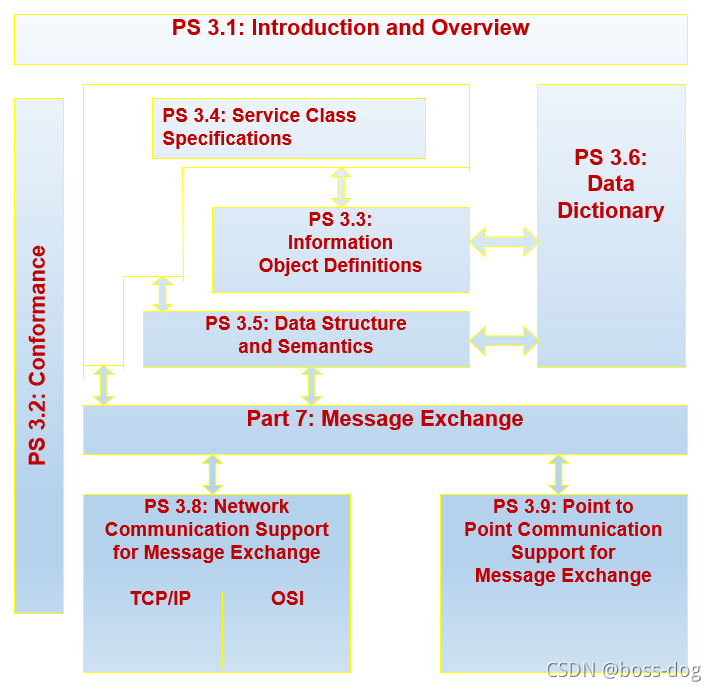

整个DICOM标准概述

- PS 3.1: Introduction and Overview (简介和概述)

- PS 3.2: Conformance(一致性)

- PS 3.3: Information Object Definitions (信息对象定义)

- PS 3.4: Service Class Specifications (服务等级规范 )

- PS 3.5: Data Structure and Encoding (数据结构与编码)

- PS 3.6: Data Dictionary (数据字典)

- PS 3.7: Message Exchange (消息交换)

- PS 3.8: Network Communication Support for Message Exchange (对消息交换的网络通信支持)

- PS 3.9: Point‑to‑Point Communication Support for Message Exchange(用于消息交换的点对点通信支持)

- PS 3.10: Media Storage and File Format for Data Interchange(数据交换的媒体存储和文件格式)

- PS 3.11: Media Storage Application Profiles(数据交换的媒体存储和文件格式)

- PS 3.12: Storage Functions and Media Formats for Data Interchange(数据交换的存储功能和媒体格式)

- PS 3.13: Print Management Point-to-Point Communication Support(打印管理点对点通信支持)

- PS 3.14: Grayscale Standard Display Function(灰度标准显示功能)

- PS 3.15: Security Profiles(安全配置文件)

- PS 3.16: Content Mapping Resource (2001)(内容映射资源(2001))